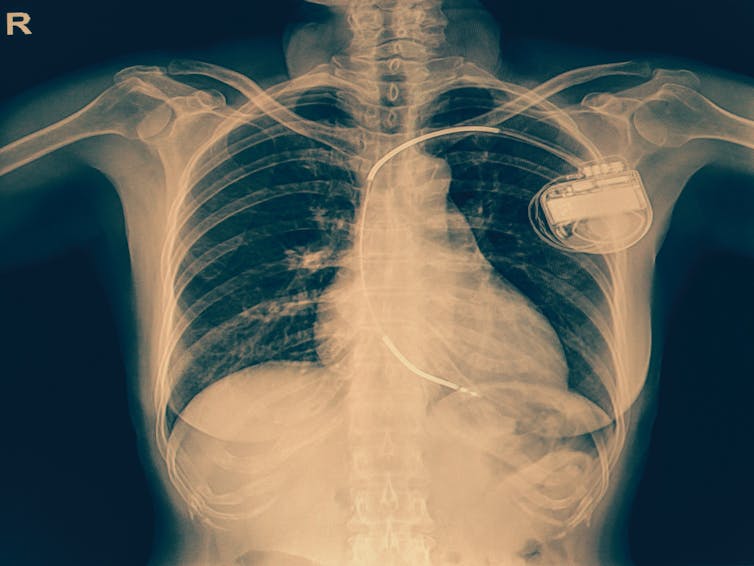

Pacemakers, and another type of implantable cardiac device called implantable cardioverter defibrillators, are both used widely in health care.

Implantable cardioverter defibrillators regulate the heart’s rhythm in people who experience heart rhythm disorders, such as ventricular arrhythmias. These devices can also deliver defibrillation (a shock) to restore a normal heart rhythm in the event of a sudden, life-threatening arrhythmia.

Around 200,000 Australians have a pacemaker or defibrillator implanted. It’s also now common to have a dual-function implantable cardioverter defibrillator and pacemaker.